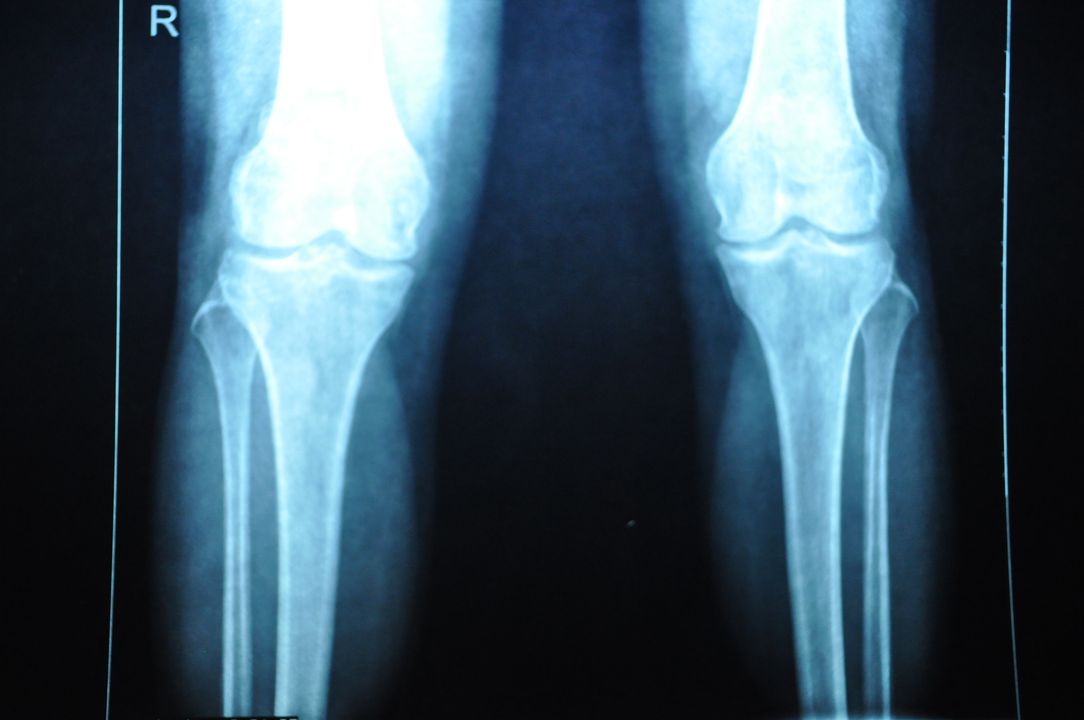

X片检查